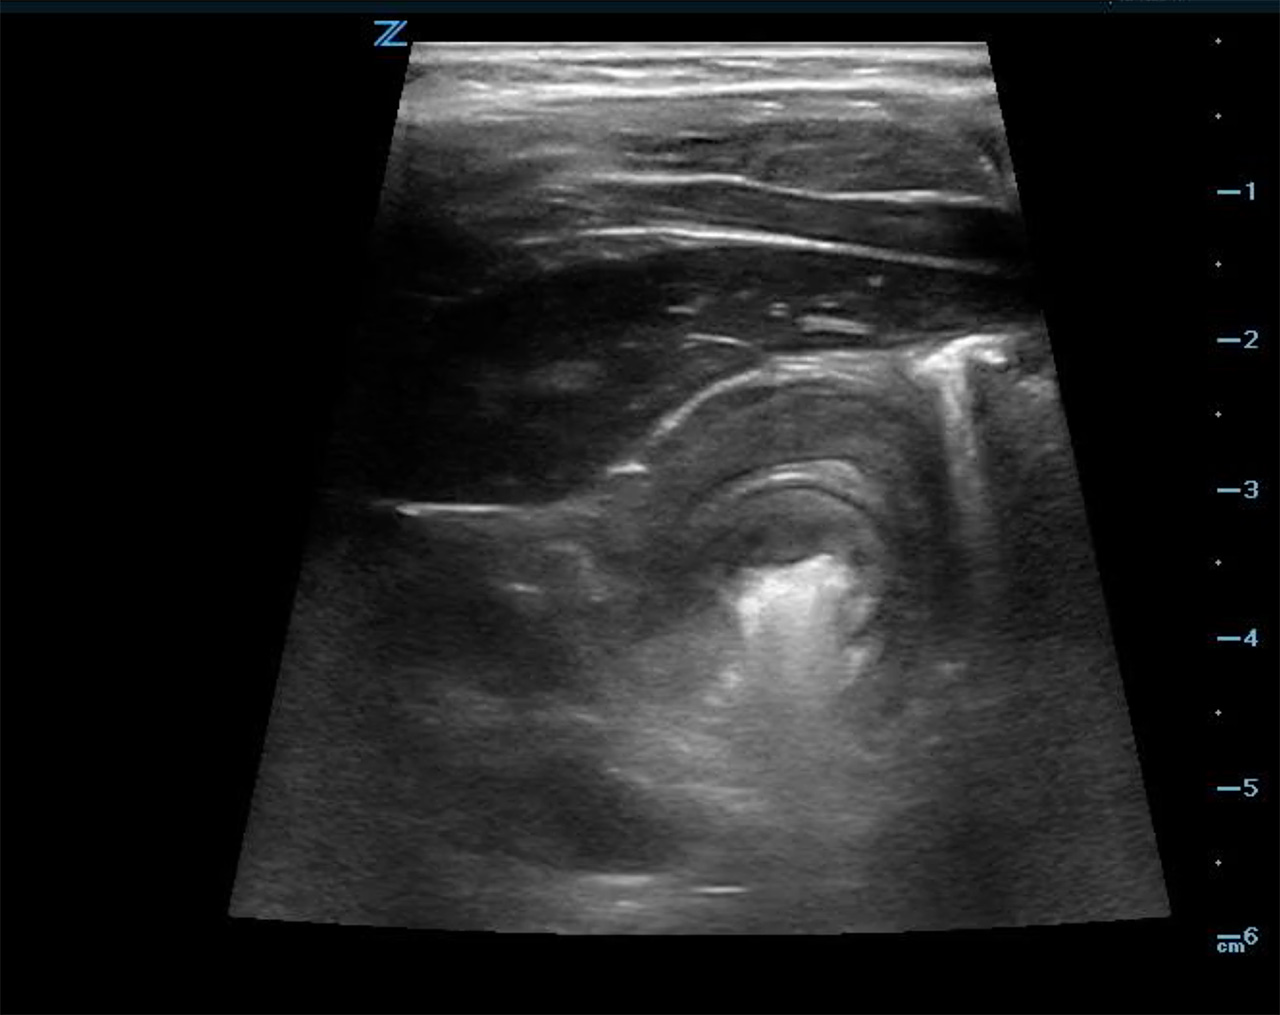

- In the transverse axis, a target or doughnut sign, is seen. This is a cross sectional view of a mass made up of invaginated bowel intussusceptum and receiving bowel intussuscipiens, which creates the appearance of concentric rings. (Fig. 6b)

- Figure 6b. Image in short axis of ileocolic intussusception